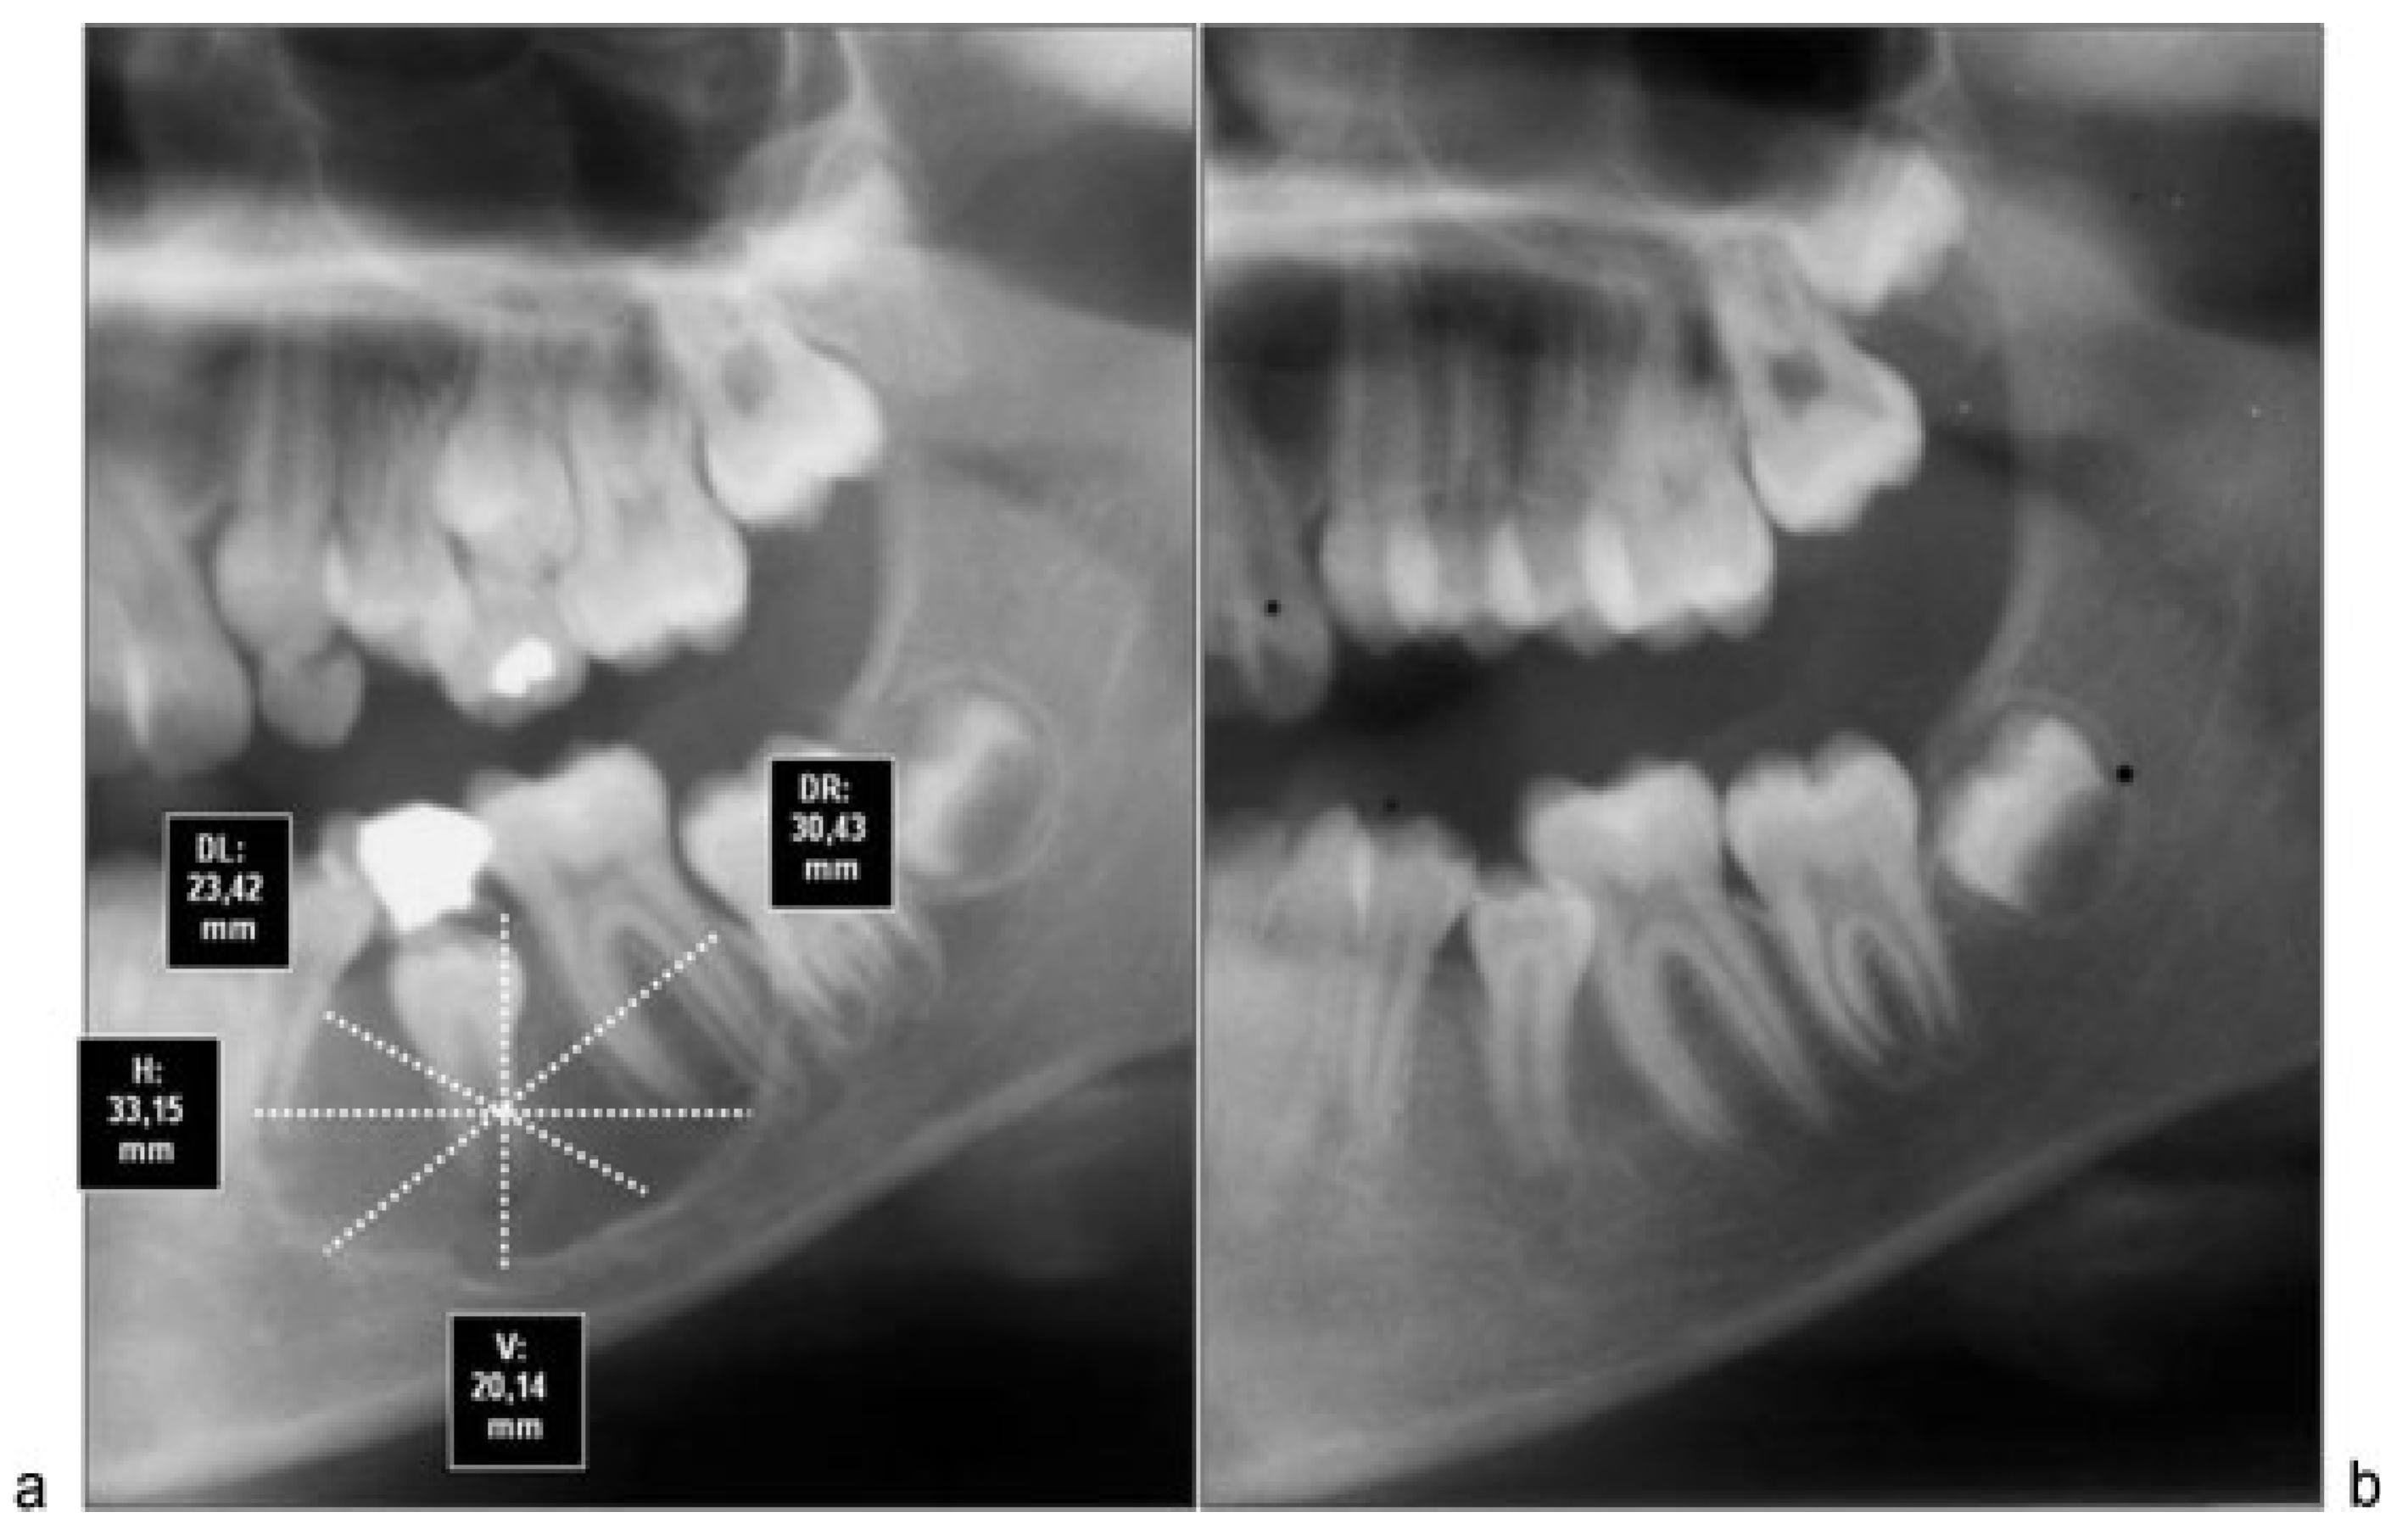

Although computed tomography provides better information about bone regeneration after surgery, to prevent high radiation dose panoramic radiographs can be considered enough for the purpose of postoperative control, so that we choose this last option (Figure 2a,b, Figure 3a,b and Figure 4a,b).

Figure 2. (a) Immediate postoperative radiograph of patient 3 with linear measures after X-ray calibration with Nemoceph program. (b) Postoperative radiograph 12 months after surgery with total bone regeneration signs in residual cavity.